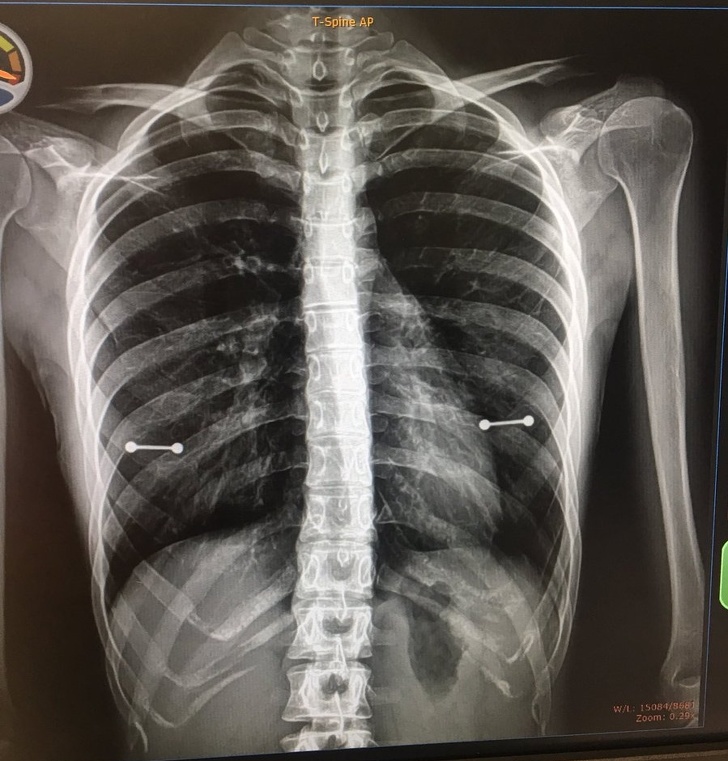

“Mi madre se enteró de esta forma de que tengo los pezones perforados”